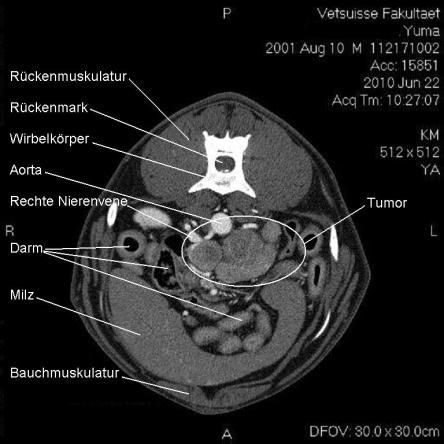

Computertomogramm

Die Computertomographie (CT) liefert mittels eines röntgenähnlichen Verfahrens ein dreidimensionales Bild des untersuchten Körperteils. Da das untersuchte Tier vollständig ruhig liegen muss, wird Yuma zur Untersuchung narkotisiert.

Im CT wird ersichtlich, dass sich der Tumor, welcher von der linken Nebenniere ausgeht, schon sehr weit in das Gefässystem von Yuma vorgearbeitet hat. Krebsausläufer finden sich wie erwartet in der Hohlvene, aber auch in der Nierenvene sowie in einer weiteren grossen Vene. Der Geschwulst ist somit inoperabel.